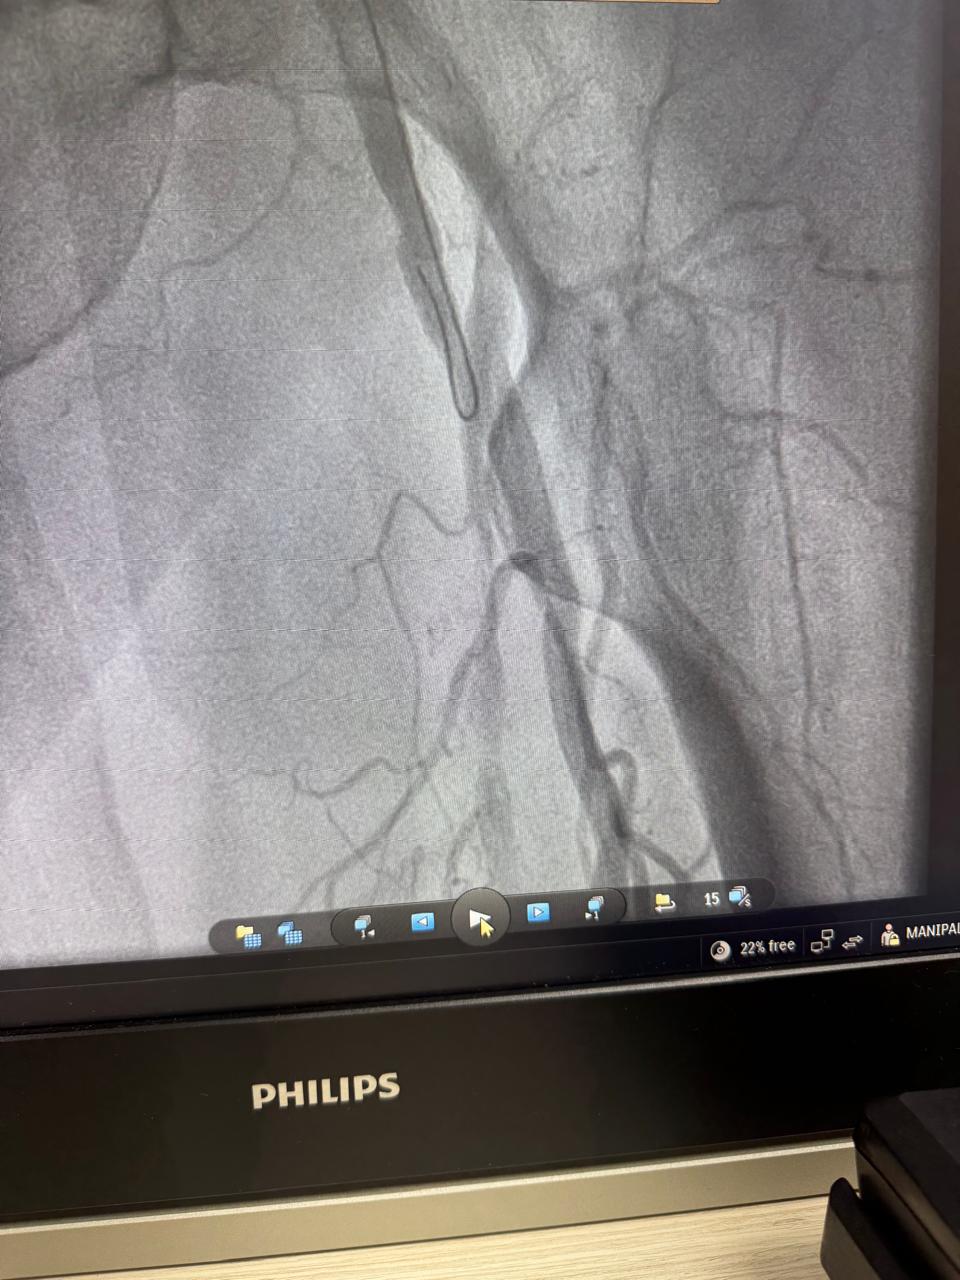

Critical stenosis in right iliac artery. Right iliac artery stenting done